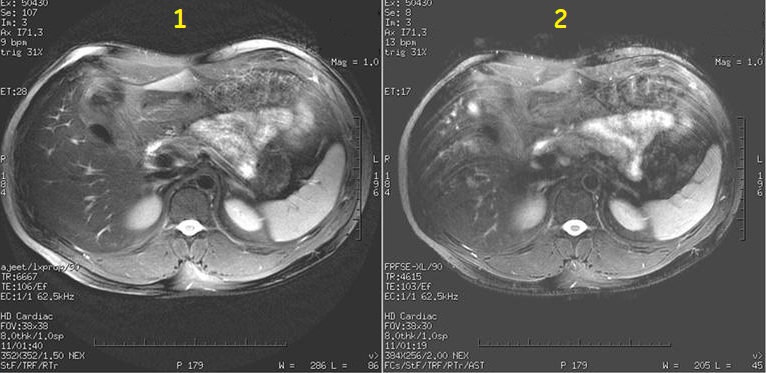

PROPELLER produces T1 and T2-weighted, free-breathing abdominal scans (for example liver and pelvis) for patients with irregular breathing patterns. It also reduces flow and other motion artifacts.

Figure 2. Motion reduction Image comparison

Table 2. Image legend

Number

Description

1

PROPELLER image

2

FSE image